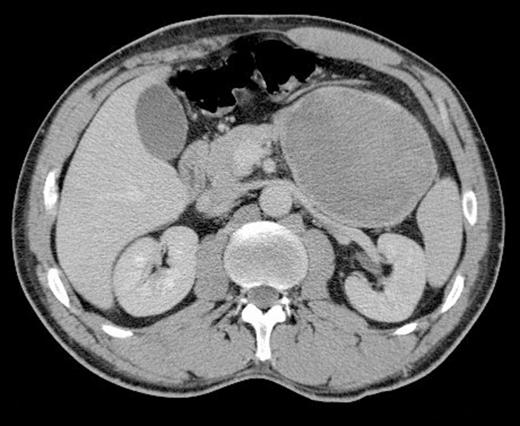

A subsequent CT scan showed an 18cm x 8cm mass related to the stomach that was displacing other organs in the left upper quadrant (Figure 2). The scan also revealed the presence of a small splenic aneurysm separate to this lesion.

Axial CT scan showing a large lesion related to the stomach in the left upper quadrant